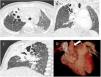

Niña de 6 años con albinismo óculo-cutáneo tipoIII que presenta neumonía al nacimiento en el lóbulo superior derecho (LSD) y posteriormente infiltrado persistente en la misma localización (fig. 1). Se realiza tomografía computarizada (TC) pulmonar que demuestra atelectasia parcial del LSD con bronquiectasias quísticas en los segmentos apical y anterior, cayado aórtico derecho y dilatación de la arteria pulmonar (fig. 2). Se realiza broncoscopia flexible en la que se aprecia, próximo a carina, bronquio traqueal derecho al que se intenta acceder sin éxito por colapso de su luz, protrusión de mucosa en la entrada de bronquio principal derecho y disminución de calibre de la entrada de LSD, con identificación de dos luces obliteradas (de bronquio de segmento anterior y posterior) (vídeo 1).

Los hallazgos sugieren malformación tipo bronquio traqueal por desplazamiento del bronquio segmentario apical del LSD1 y compresión del mismo junto al segmento anterior por la aorta, de localización derecha, con formación de bronquiectasias, una asociación infrecuente con el bronquio traqueal2,3. Ante la buena evolución clínica de la paciente se toma una actitud expectante, sin presentar infecciones pulmonares en la actualidad. La TC de control 4años después revela una atelectasia de aspecto fibroso residual retráctil y bronquiectasias (fig. 3).